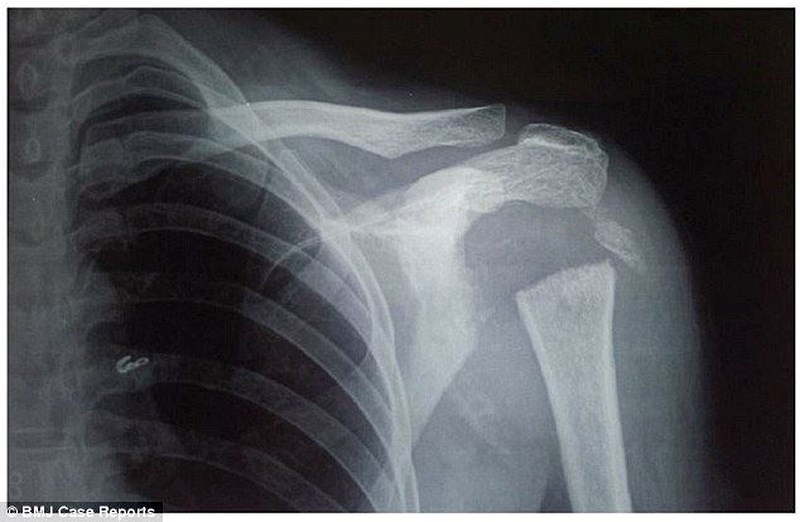

Các bác sĩ tại học viện Khoa học Y dược Pondicherry nhận thấy phần vai của cô mềm nhũn và cô có thể xoay tay 180 độ. Sau khi dùng tia X để kiểm tra, họ phát hiện phần đầu xương cánh tay của cô - phần xương hình tròn nối liền cánh tay và bả vai đã không còn.

Ảnh chụp X-quang cho thấy phần xương nối liền bả vai và cánh tay của cô đã không còn. Ảnh: BMJ Case Reports.